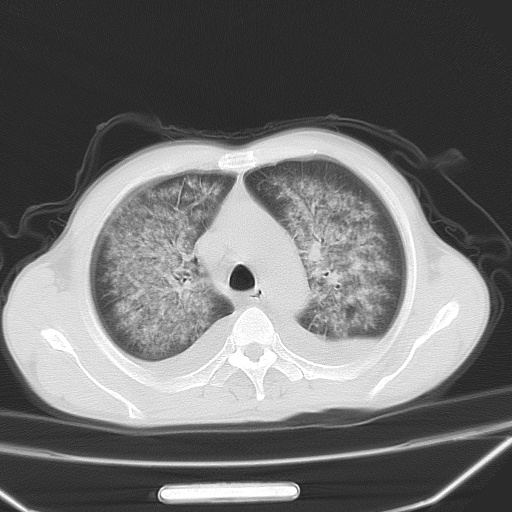

男、42岁、咯血3天。既往有甲亢、贫血、血尿蛋白尿史多年。血象:wbc:6.   中性粒:70.6%。

双肺野对称性磨玻璃影,分布于内中带,双侧胸水,患者有咯血。

双肺野广泛对称性磨玻璃影、实变影,以肺门为中心,主要分布于内中带,符合典型肺泡性肺水肿;伴双侧胸腔少量游离积液。结合患者既往病史且咯血就诊,支持多因素(尿毒症等)所致之肺水肿、肺出血、胸水;影像表现暂不考虑心源性水肿,且症状也不太符。需密切随诊结合临床治疗等进一步明确。